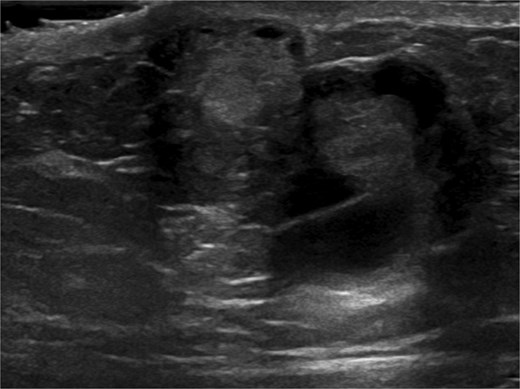

A 63-year-old male with a past medical history of heavy daily tobacco use, COPD, and a left breast leiomyoma diagnosed in 2018 presented to a general surgeon with a nonhealing left breast abscess. The patient had a persistent 3 cm retroareolar mass despite multiple incision and drainage procedures. On exam, the left axillary lymph nodes were unremarkable and the nipple, while not inverted, was chronically distorted, indurated, and inflamed. The persisting mass and inflammation were initially concerning for inflammatory breast cancer. Superficial biopsy by both a dermatologist and general surgeon were equivocal. Diagnostic mammogram and targeted left breast ultrasound revealed a retroareolar 3.3 × 3.6 × 2.7 cm heterogenous mass, corresponding to the area of palpable concern (Figs 1 and 2).

Ultrasound-guided core needle biopsy of the mass showed dissociated fragments of cribriform-like and papillary-like carcinoma (Figs 3 and 4).

Ultrasound of retroareolar area of palpable concern – first view.

Ultrasound of retroareolar area of palpable concern – second view.